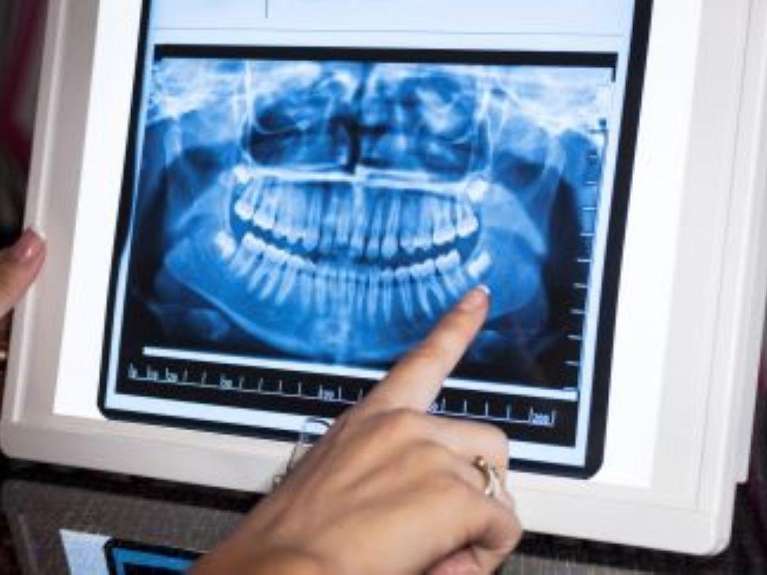

Digital X-Rays

Digital x-rays are a safe way for dentists to diagnose dental conditions before they become more significant. Using up to 80 per cent less radiation than traditional x-rays, we can take high-resolution images to see things that aren’t visible to the naked eye, such as tooth decay, infections, bone levels, broken roots, cysts or tumors. We can store your electronic images to use for comparison later.

Panoramic X-Rays

A panoramic x-ray can show us all your teeth simultaneously because it moves completely around your head. When we plan dental surgeries or implant placement, panoramic x-rays can show us your teeth, jaw joints, bone levels and sinuses.